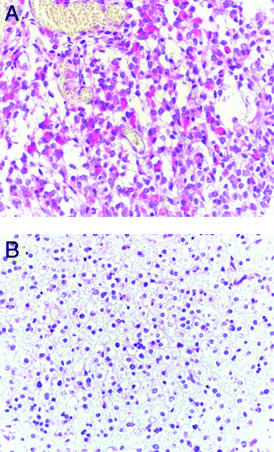

Glioma. Gliomas are the most common nervous system tumor in adults, with glioblastomas, astrocytomas and oligodendrogliomas representing the most frequent subtypes (66). Wang et al used immunohistochemistry to examine the expression of Trk receptors in a cohort of glioma cases. Interestingly, they found that TrkA, TrkB and TrkC immunoreactivity was only found in astrocytomas but not in oligodendrogliomas (90). Strikingly, Trk expression appeared to be limited to the astrocytic component in mixed gliomas (oligoastrocytomas) (see Figure 1). Moreover, Trk staining was also observed in reactive astrocytes surrounding tumors.

Figure 1.

A. Astrocytic component in a mixed oligoastrocytoma showing distinct cytoplasmic TrkC immunoreactivity (red). Paraffin section, hematoxilin counterstain; ×350. B. The oligodendroglial component of the same tumor lacks TrkC immunoreactivity. Paraffin section, hematoxilin counterstain; ×350.